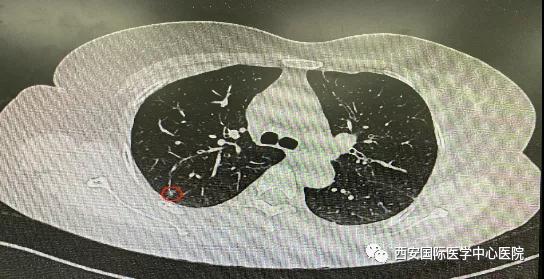

日前,西安國際醫(yī)學(xué)中心醫(yī)院胸科醫(yī)院胸外科二病區(qū)成功開展LungPro全肺導(dǎo)航下經(jīng)支氣管鏡注入亞甲藍(lán)染色劑標(biāo)記結(jié)節(jié)位置,行精準(zhǔn)肺段切除術(shù),成為西北地區(qū)首例“Lung Pro全肺診療導(dǎo)航系統(tǒng)聯(lián)合單孔胸腔鏡下右肺上葉后段切除術(shù)”,填補(bǔ)了西北地……